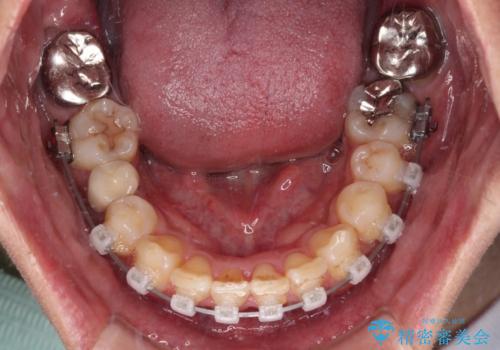

- クリアブラケット

- 2年8ヶ月

補助装置を併用することで効率的に八重歯や正中位置の改善を達成することができました。